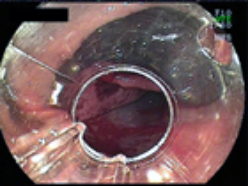

2.当科が開発した先端細径透明フード(STフード)とヒアルロン酸ナトリウム局注液を使用して、内視鏡下に電気メスで病変を剥離していきます。

早期大腸癌に対するESD

1.直腸に認められたφ7cmの病変(左:通常観察、右:色素内視鏡観察)

2.当科が開発した先端細径透明フード(STフード)とヒアルロン酸ナトリウム局注液を使用して、内視鏡下に電気メスで病変を剥離していきます。